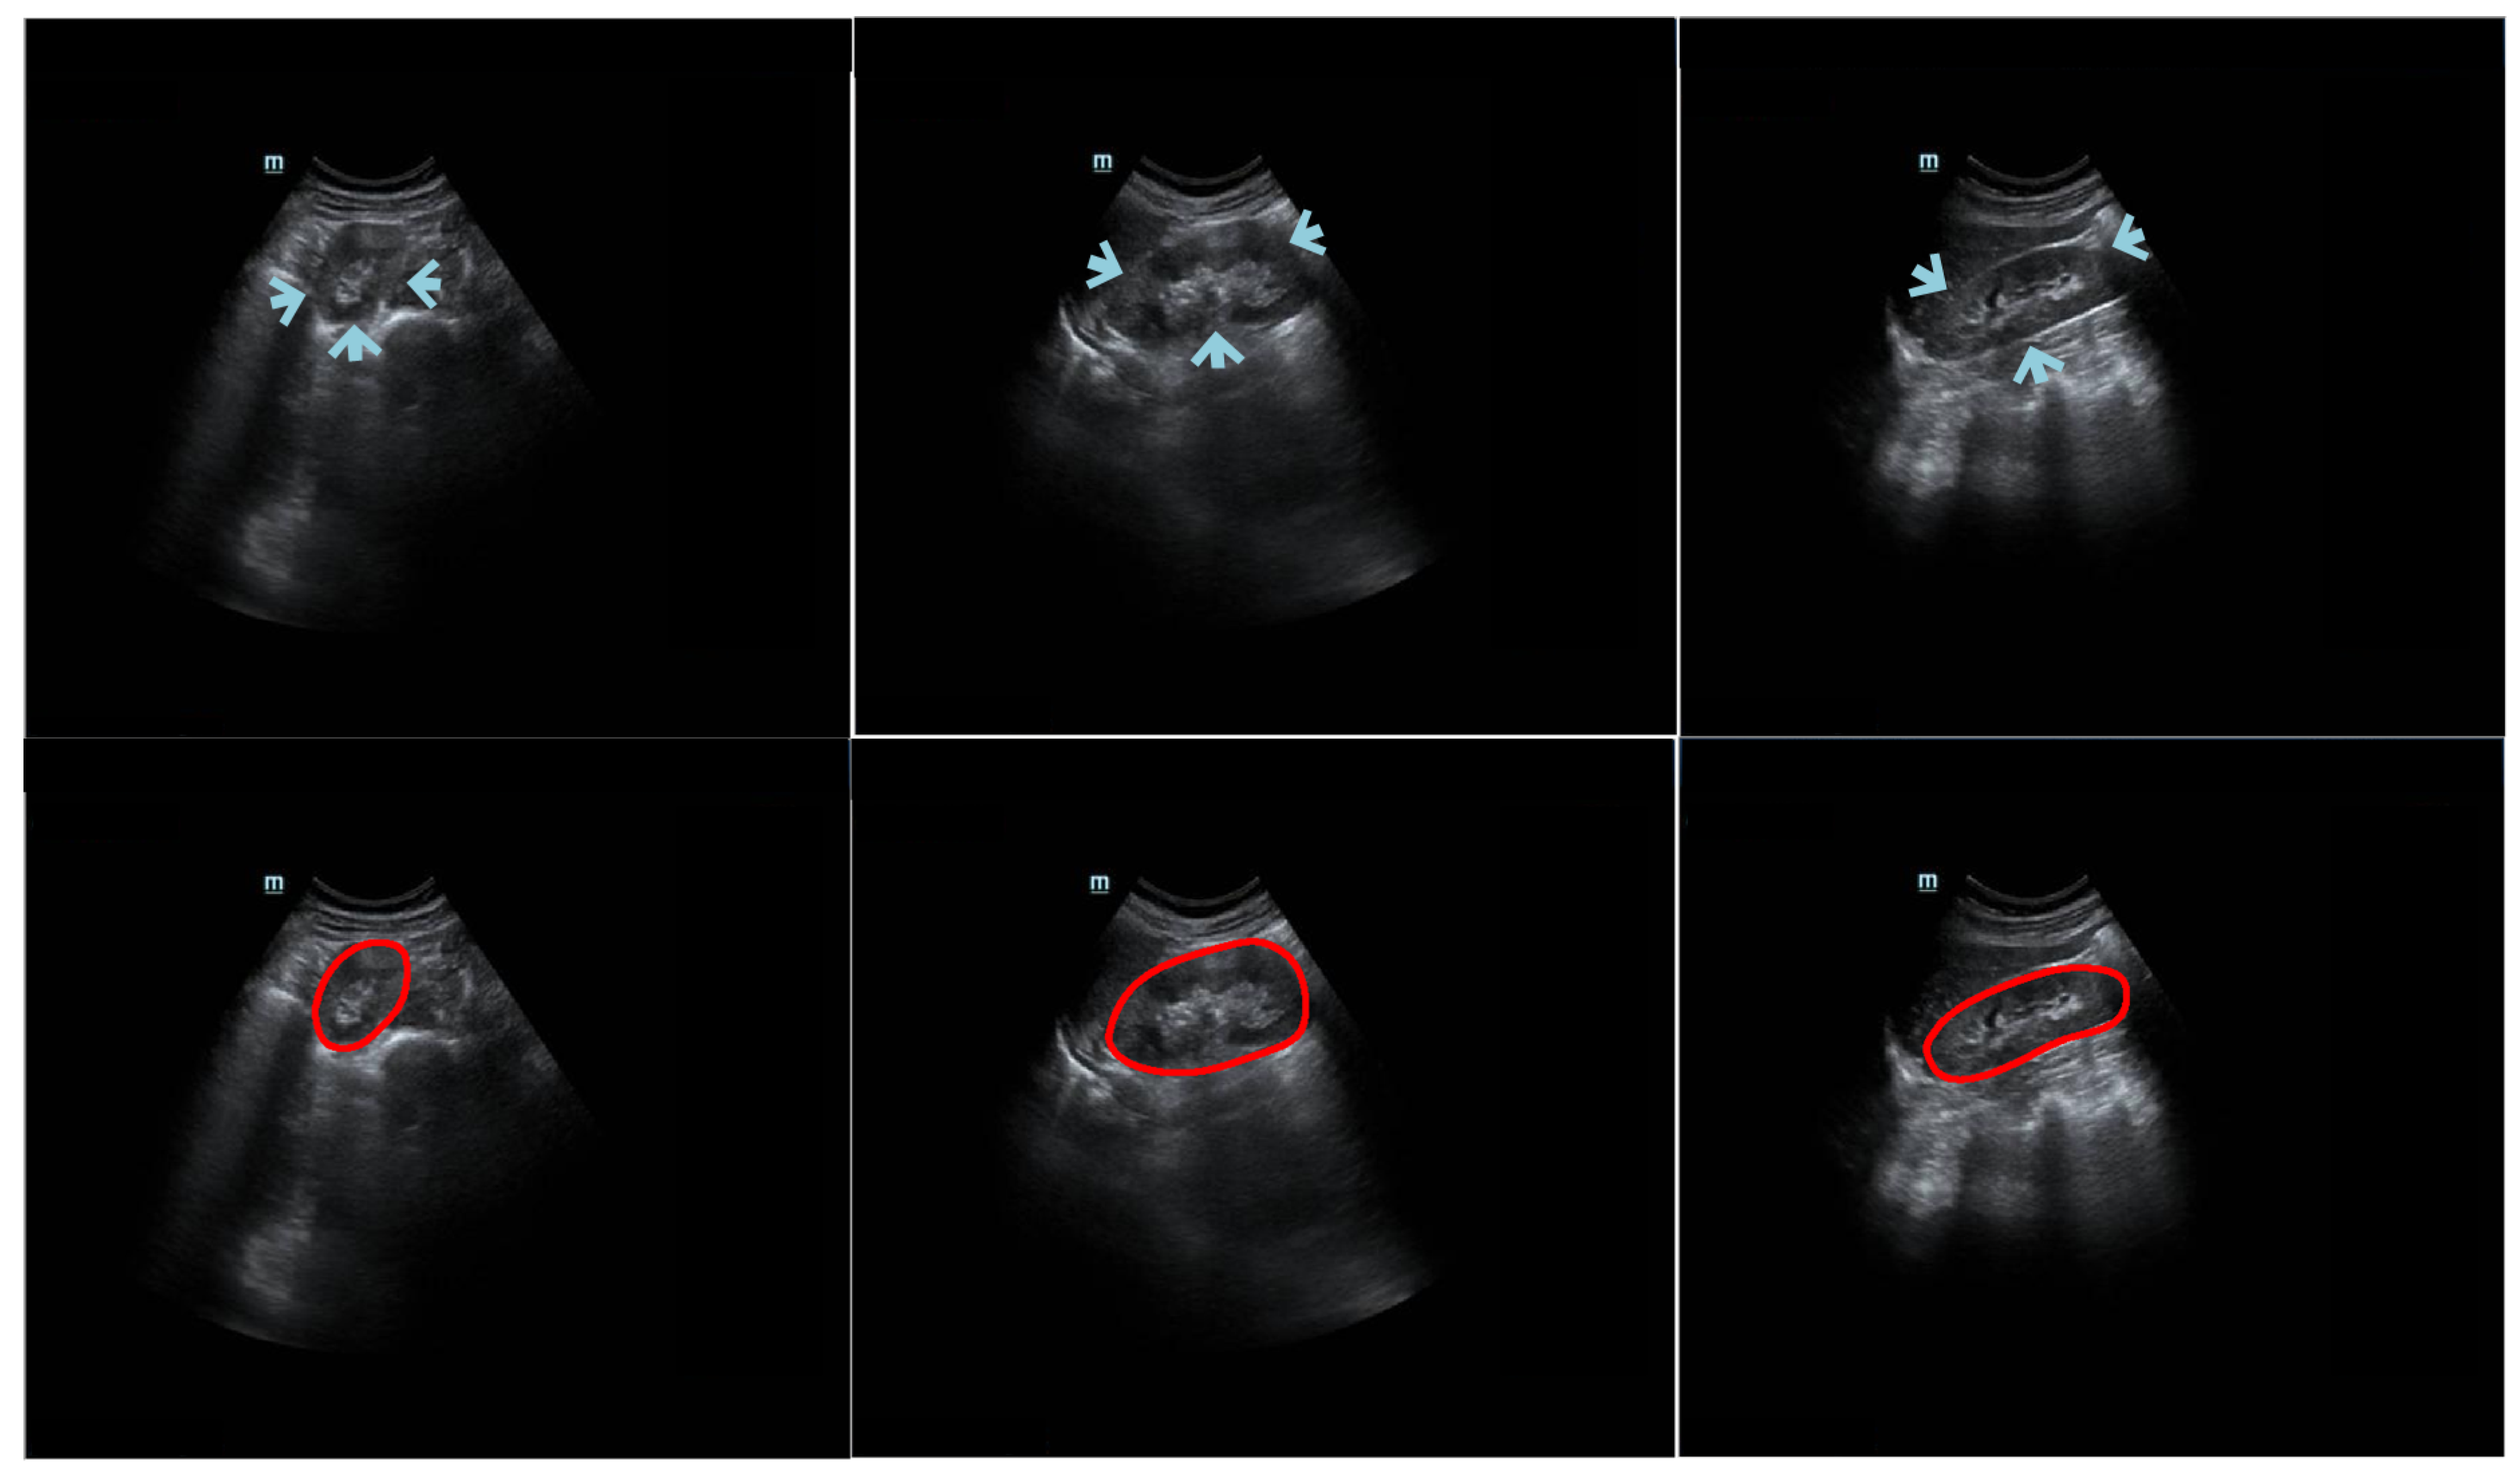

Figure 1.

Example trans-abdominal US kidney images. Portions of the kidney boundary, pointed to by arrows, do not have high contrast with the surrounding tissue. The first column shows an axial image, and the second and third columns show sagittal images. The second row displays the corresponding ground truth of the original data in the first row. The red circles represent the contour manually delineated by the professional radiologists.